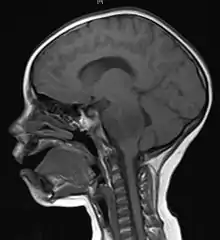

Brain metastasis in the right cerebral hemisphere from lung cancer, shown on magnetic resonance imaging

Medical imaging plays a central role in the diagnosis of brain tumors. Early imaging methods – invasive and sometimes dangerous – such as pneumoencephalography and cerebral angiography have been abandoned in favor of non-invasive, high-resolution techniques, especially magnetic resonance imaging (MRI) and computed tomography (CT) scans,[38] though MRI is typically the reference standard used.[41] Neoplasms will often show as differently colored masses (also referred to as processes) in CT or MRI results.